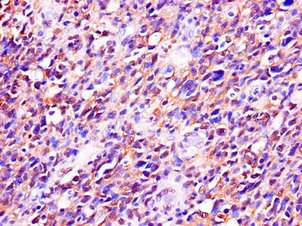

Immunohistochemistry of paraffin-embedded human glioma using CSB-PA897546LA01HU at dilution of 1:100